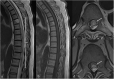

Background: Vascular lesions of the spinal cord are rare but potentially devastating conditions whose accurate recognition critically determines the clinical outcome. Several conditions lead to myelopathy due to either arterial ischemia, venous congestion or bleeding within the cord. The clinical presentation varies, according with the different aetiology and mechanism of damage.

Purpose: The aim is to provide a comprehensive review on the radiological features of the most common vascular myelopathies, passing through the knowledge of the vascular spinal anatomy and the clinical aspects of the different aetiologies, which is crucial to promptly address the diagnosis and the radiological assessment.